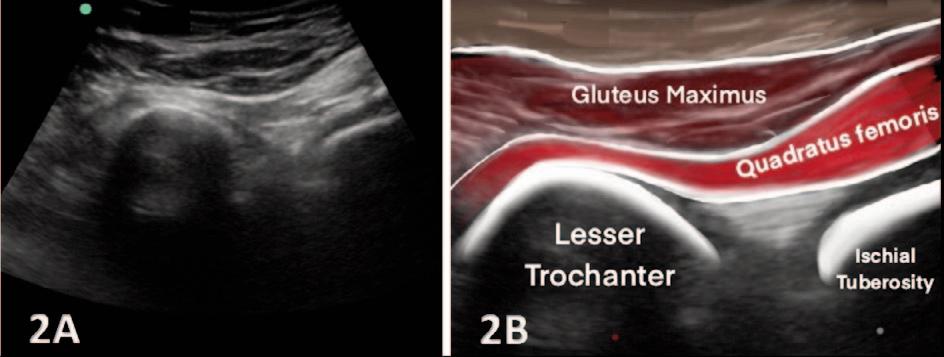

MSK ULTRASOUND BITES: Tips and Tricks

The Utilization of Diagnostic Musculoskeletal Ultrasound in the Evaluation for Ischiofemoral Impingement: A Perspective for Rehabilitation Providers. Manske RC, Wolfe C, Page P, Voight M, Bardowski B.